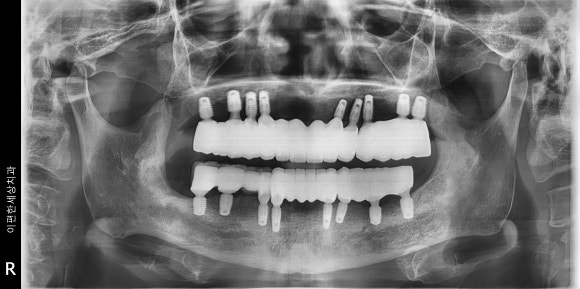

이편한세상치과 진단 장비

이편한세상치과에서는 반드시

3D CT 촬영을 통해 뼈의 두께, 높이, 신경 위치를 정밀 분석합니다.

단순한 엑스레이로는 보이지 않는 뼈 속 구조를 확인해야

임플란트가 얼마나 깊이, 어떤 각도로 심겨야 하는지 알 수 있거든요😊

실제 뼈이식 과정입니다 :)

특히 상악동(위턱 뒤쪽)처럼 뼈가 얇은 부위는

뼈이식이나 상악동 거상술이 필요한 경우도 있는데요.

사실 이런 과정을 생략하면

임플란트가 오래 버티기 어렵습니다..

임플란트는 ‘심는 기술’보다 ‘심을 수 있는 기반',

즉 '뼈의 상태’를

정확히 보는 데서 시작되기 때문이죠.

잇몸이 약한 분이라 뼈이식을 동반해서 치료해 드렸습니다^^

촬영일 : 241206